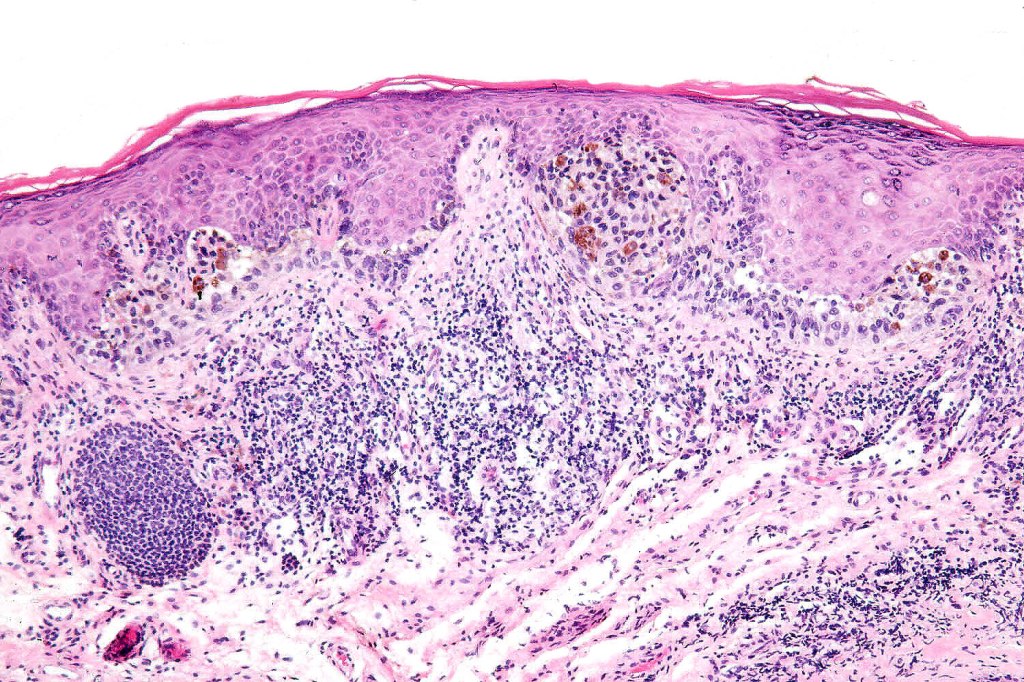

Histological features

•Junctional/compound

•Large dyscohesive nests with retraction artifact, not restricted to the tips of the epidermal ridges

•Heavy pigmentation (sometimes gray/green)

•Bridging common, often over multiple rete ridges

•Variable atypia (can be marked)

•Central pagetoid spread

•Superficial dermal atypia

•Junctional mitoses sometimes present, dermal mitoses+/-, can be multiple but never atypical

•Dermal fibrosis (sometimes lamellar)

. HMB45 shows gradation with depth, Ki67 is low